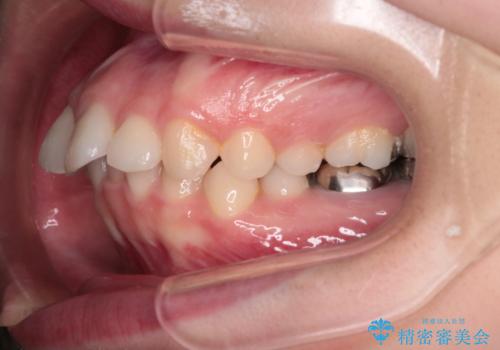

【インビザライン】前歯を引っ込めたい

- 前歯が出ていることを主訴に来院された患者様です。

抜歯を希望されなかっため、臼歯部の遠心移動やIPRを行い配列を行っています。

抜歯をしていない矯正となるため、口元に大きな変化は認められません。